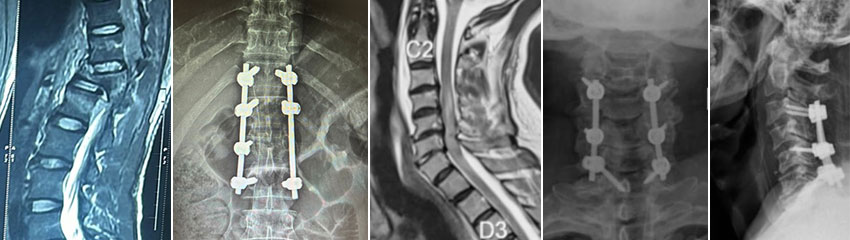

His approach includes a thorough assessment of each patient’s condition, including imaging studies such as MRI, CT scans, and X-rays, to determine the most effective treatment plan. Dr. Naik's surgical expertise ensures minimal complications and promotes faster recovery, making him a trusted name in spine surgery. Find Here Best Spine Fracture Treatment in Vashi.

Spine fractures, often caused by trauma, osteoporosis, or sports injuries, require immediate and specialized care. As the Best Spine Surgeon in Vashi, Dr.Ashish Naik provides comprehensive treatment for spine fractures, including both surgical and non-surgical options.

For minor fractures, Dr. Naik may recommend bracing, physical therapy, and medications to promote healing. In more severe cases, he employs advanced surgical techniques such as vertebroplasty, kyphoplasty, or spinal fusion to stabilize the spine and restore function. His personalized approach ensures optimal outcomes, helping patients regain mobility and live pain-free.

Cervical myelopathy is a serious condition resulting from spinal cord compression in the neck. It can lead to symptoms like numbness, weakness, and difficulty with coordination. Dr.Ashish Naik, recognized as the Best Spine Surgeon in Vashi, specializes in diagnosing and treating cervical myelopathy, offering both conservative and surgical options. Early detection is crucial for effective treatment. Dr. Naik’s expertise in advanced imaging and diagnostic techniques allows him to pinpoint the severity of the condition accurately. Depending on the case, he may recommend non-surgical treatments like physical therapy and medications. However, for more advanced cases, surgical intervention such as decompression or fusion surgery may be necessary to alleviate pressure on the spinal cord and prevent further damage.